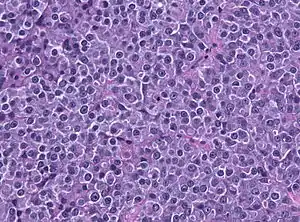

A prolactinoma is a benign tumor (adenoma) of the pituitary gland that produces a hormone called prolactin. It is the most common type of functioning pituitary tumor.[1] Symptoms of prolactinoma are due to too much prolactin in the blood (hyperprolactinemia), or those caused by pressure of the tumor on surrounding tissues.

Based on size, a prolactinoma can be classified as a microprolactinoma (<10 mm diameter) or macroprolactinoma (>10 mm diameter).

Autopsy studies indicate that 6-25% of the U. S. population have small pituitary tumors.[7] Forty percent of these pituitary tumors produce prolactin, but most are not considered clinically significant. Clinically significant pituitary tumors affect the health of approximately 14 out of 100,000 people. In non-selective surgical series, this tumor accounts for approximately 25-30% of all pituitary adenomas.[8] Some growth hormone (GH)–producing tumors also co-secrete prolactin. Microprolactinomas are much more common than macroprolactinomas.